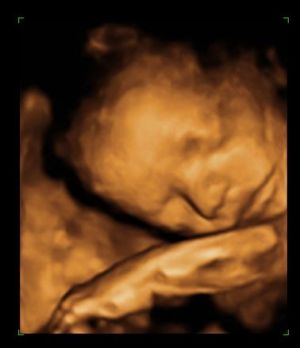

A 4D-t itt csinálták (BP-en ez a legolcsóbb hely :wink: )

www.4dgenesis.hu

Egy másik kép :P

Kép Manóka